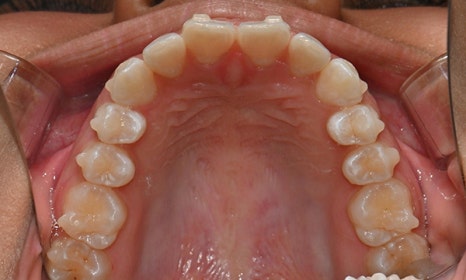

위아래 앞니 사이가 벌어져서 공간이 있었고, 앞니에 약간씩 배열이 틀어진 덧니가 있었습니다. 정면에서 보았을 때 윗니와 아래 앞니가 깊게 물려서 아래 앞니가 잘 보이지 않는 과개교합 양상을 보이고 있었습니다. 또한 왼쪽 아래 작은 어금니가 90도 앞으로 돌아가서 좌측 치아 배열 및 교합이 좋지 않은 상태였습니다.

초진시 구내사진 (2025. 3.31)